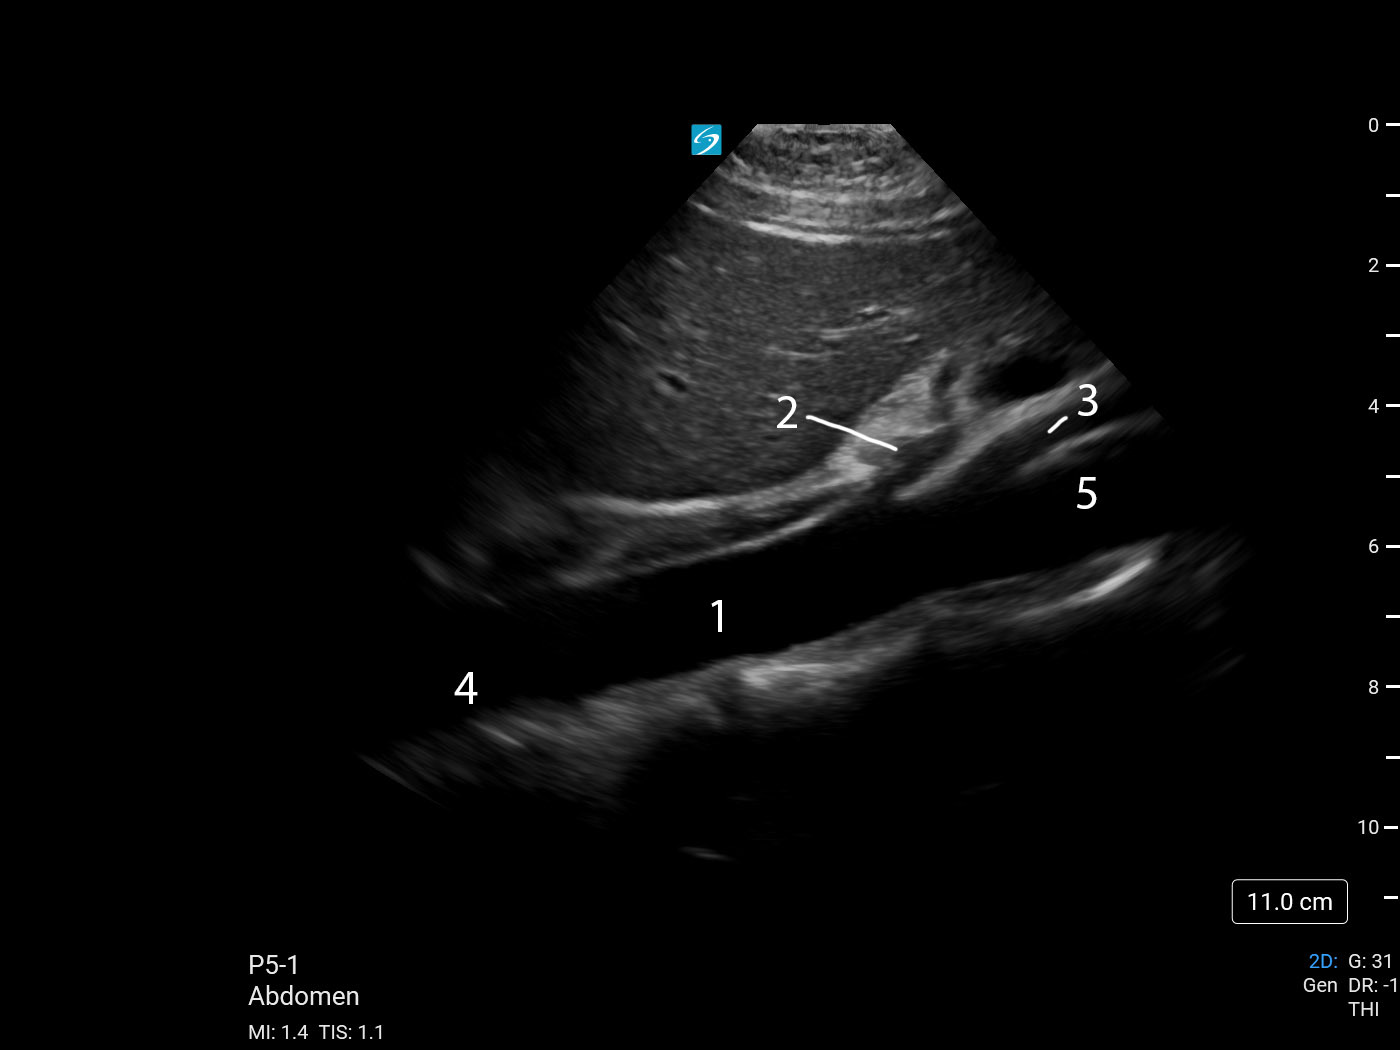

Aorta Sagittal Proximal (Sonosite PX P5-1) Image

1. Aorta

2. Celiac Axis

3. Superior Mesenteric Artery (SMA)

4. Proximal Aorta

5. Mid Aorta